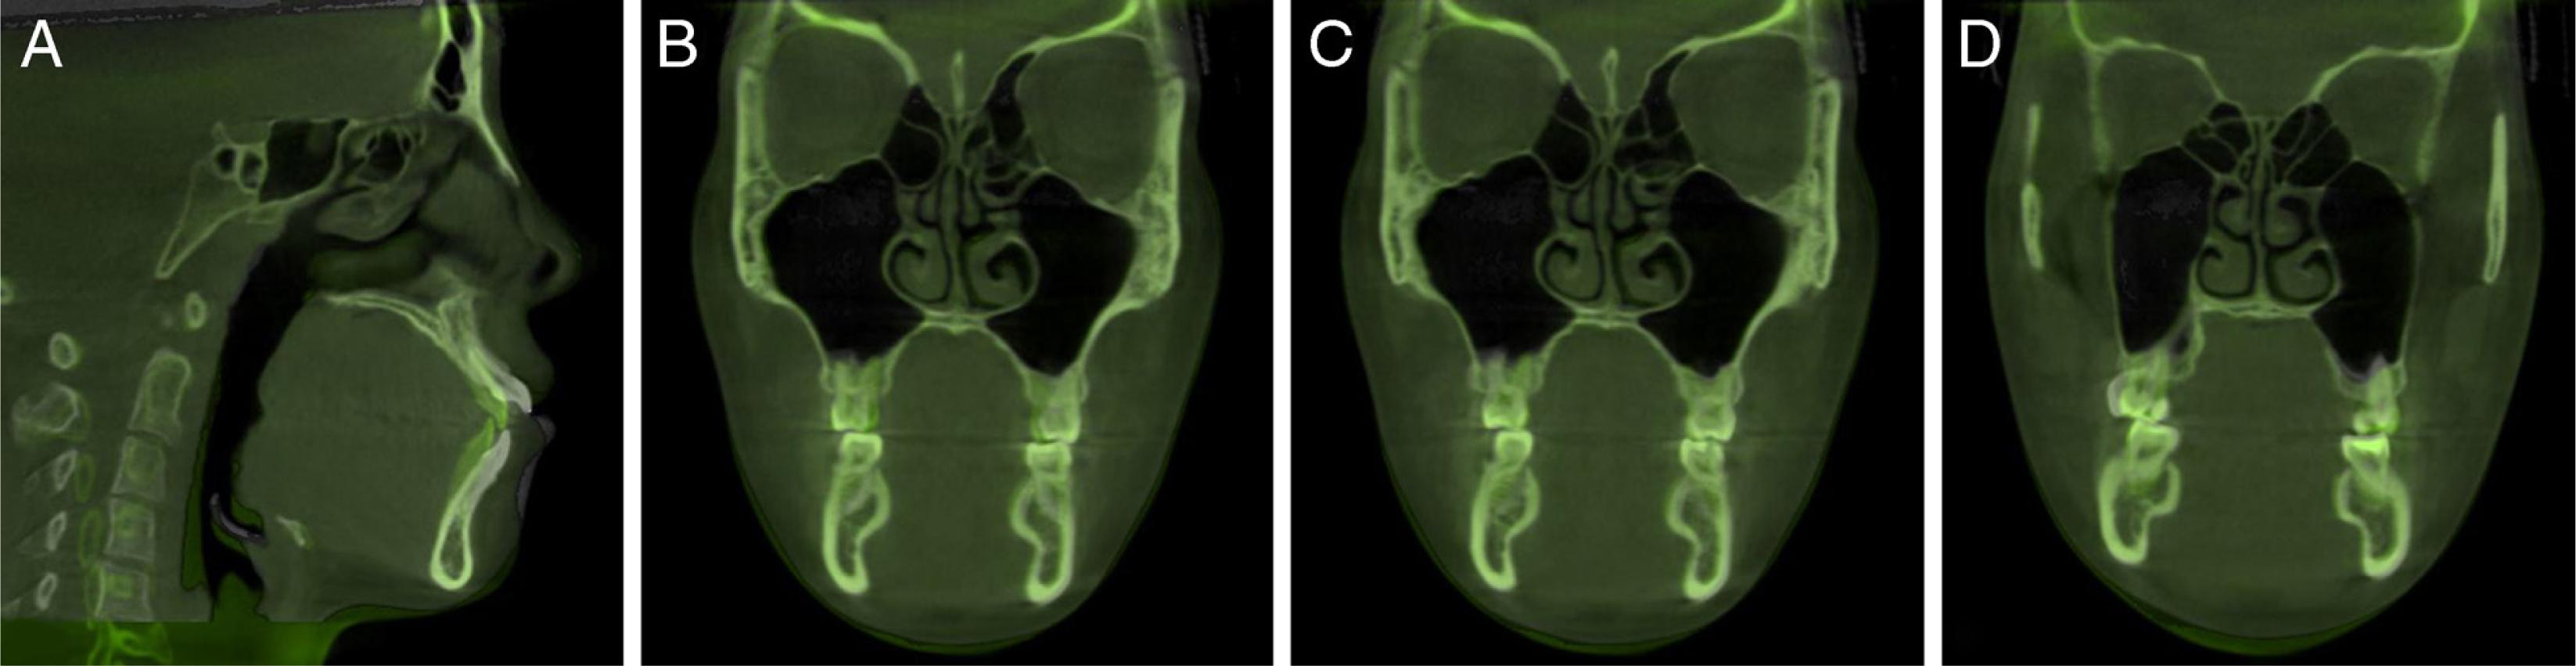

A 24-year-old female patient presented with a history of tongue thrust and mouth breathing but without a history of maxillofacial trauma or a non-nutritive sucking habit. The diagnostic records revealed that, based on the E line, the patient had a convex profile with a long face, a decreased nasolabial angle, a protrusive lower lip, and a shallow mentolabial sulcus. Further, the patient had incompetent and protruded lips at rest and in contact but with mentalis strain upon forcible closure. There was also a low smile line, and the smile arc was not consonant with the curvature of the lower lip (Figure 1). An intraoral examination showed an anterior open bite with no occlusal contact from the right first premolar to the left first premolar, a bilateral Class III molar relationship, and a Class III canine relationship on the right side but a Class I relationship on the left side. An analysis of the initial study models revealed that there was an anterior dental open bite of 6 mm, a decreased overjet (the overjet and overbite were measured on digital dental models using 3-shape software), a 3 mm curve of Spee, a mandibular midline deviation (1.5 mm to the left), and arch-length discrepancies of 5 mm in the maxilla and 3 mm in the mandible. The anterior and overall Bolton ratios were compatible. The maxillary dental arch was narrow, and the upper and lower arches were unmatched. A crossbite from the upper left canine to the second premolar was also noted during the examination. The maxillary right second molar was in scissor-bite with the mandibular right second molar (Figure 2). A cephalometric analysis revealed a skeletal open bite (SN/GO-GN 48°), an increased mandibular plane angle, a counter-clockwise rotation of the ANS-PNS plane (S-N/ANS-PNS 6°), proclination of the upper incisors (UI/ANS-PNS 129°), an interincisal angle of 108°, excessive lower anterior facial height and a short upper anterior facial height (Table I). A computed tomography scan of the anterior teeth revealed adequate labial and lingual bone volumes (Figure 3A). In addition, the initial panoramic radiograph and the radiographic and clinical examinations of the temporomandibular joints revealed no obvious abnormalities (Figure 4 and 3B). The patient was diagnosed with a Class III malocclusion (S-N/ANS-PNS 6°) and skeletal open bite (SN/GO-GN 48°) with an increased mandibular plane angle, a long face, a convex profile, and lip incompetence with mentalis strain. There was also proclination of the upper incisors, a crossbite, scissor-bite, mild crowding and midline deviation.

The pre-treatment labial and lingual bone volume of anterior teeth (A) and temporomandibular joint radiograph (B).